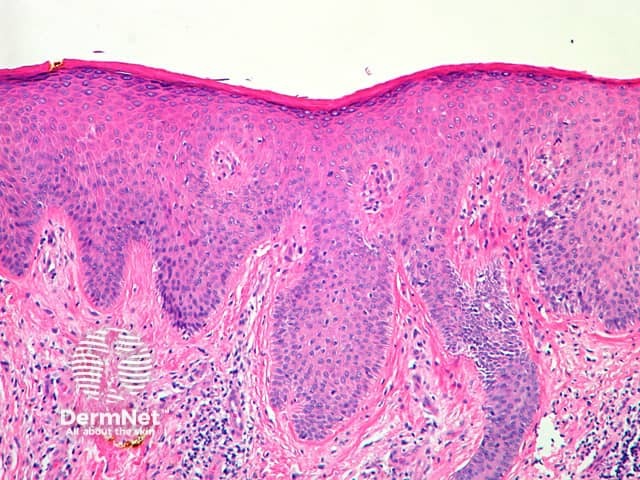

This is the most frequently encountered type of spongiotic dermatitis. The degree of spongiosis and exocytosis of inflammatory cells is mild to moderate. Irregular acanthosis and parakeratosis are additional features compared with acute spongiotic dermatitis. A superficial dermal perivascular lymphohistiocytic inflammatory infiltrate, swelling of endothelial cells, and papillary dermal oedema are present (figure 2).

Figure 2